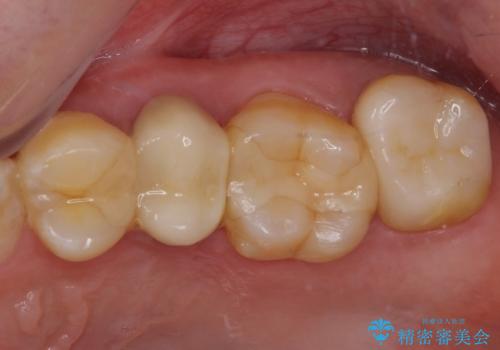

抜歯が必要な奥歯 ストローマン・インプラント補綴治療

- 近医にて奥歯の抜歯が必要と言われたとのことで来院された患者様です。

診査の結果、歯が破折しており、抜歯が必要な状態でした。

最後方歯であるため、入れ歯かインプラントかどちらかの補綴治療を行うこととなりますが、ご希望によりインプラント補綴治療を行うこととしました。

インプラントにはストローマン社のSLActiveを使用し、埋入から補綴までおよそ3か月と、短期間で治療を進めることができました。